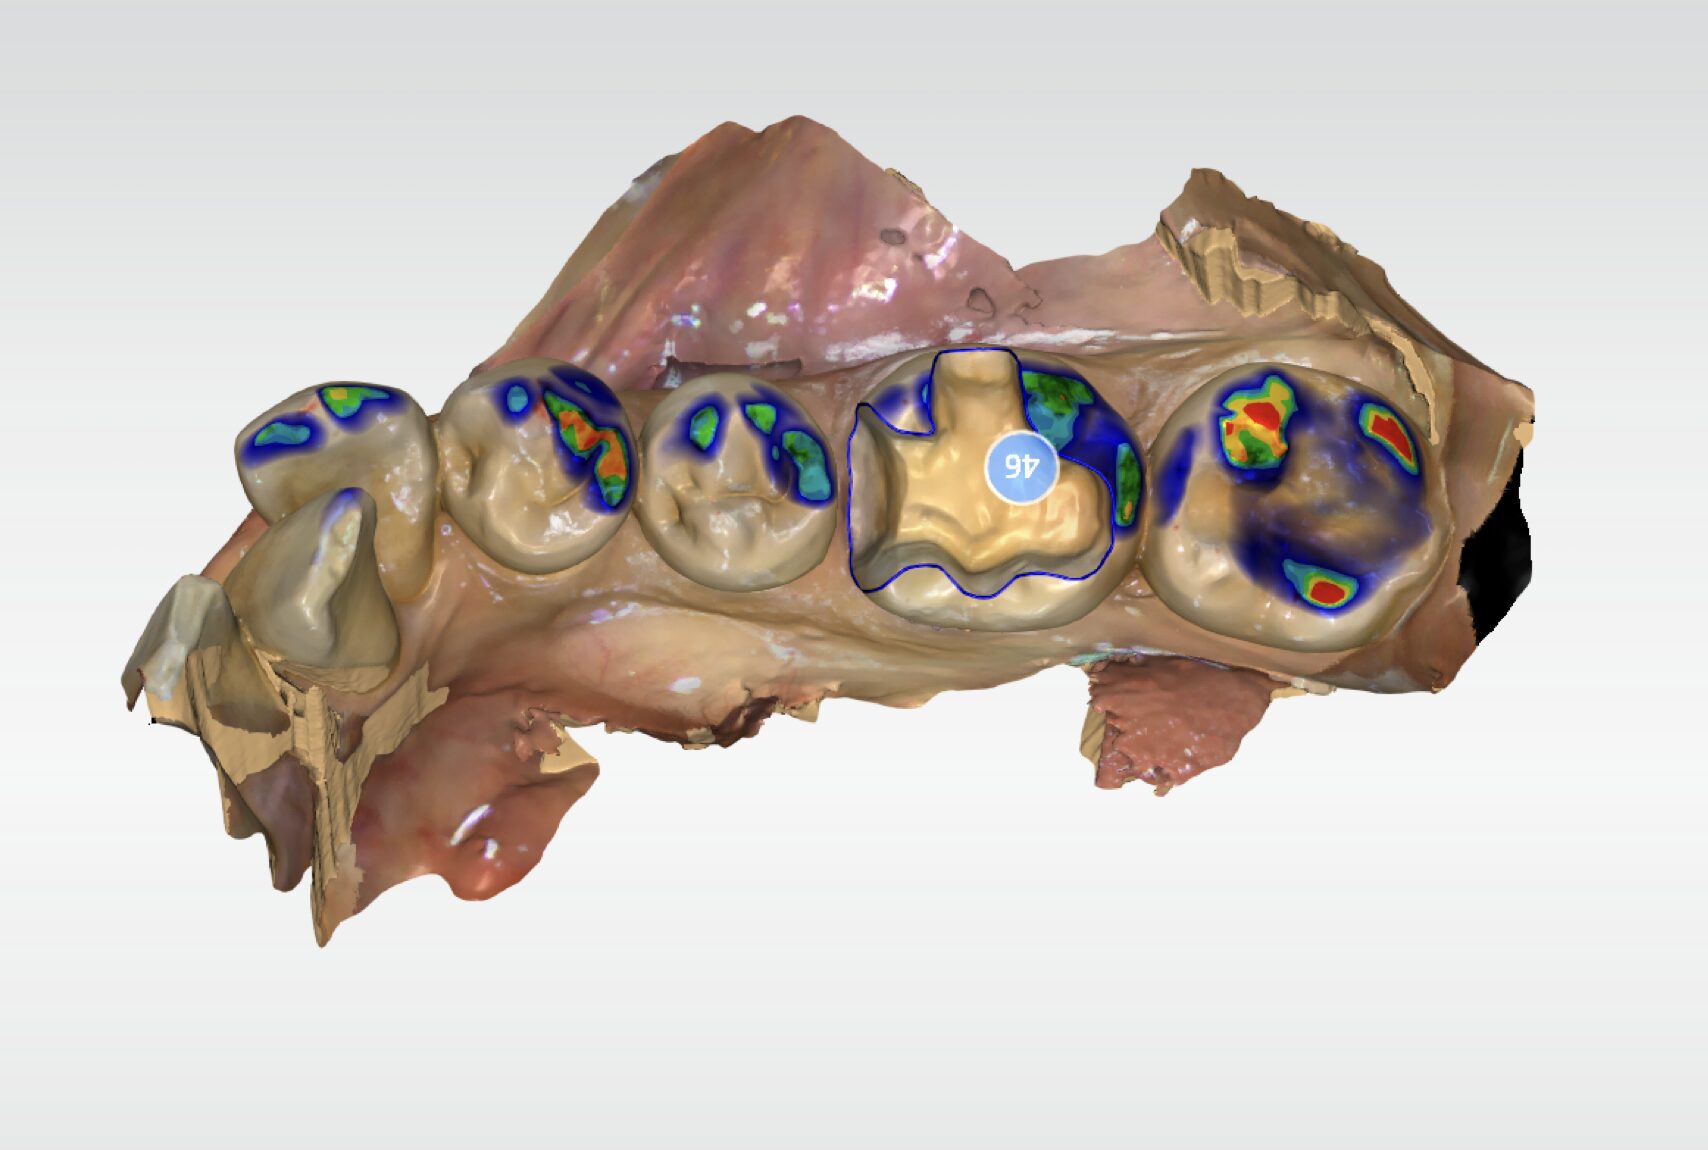

当院では、従来の粘土のような型取り材は使用しません。

小型のカメラ(口腔内スキャナー)で、お口の中をデジタルスキャンします。数十秒で、モニター上に精密な3Dデータが再現されます。

当院の特徴の一つは、スキャンしたデータをもとに院長自らがセラミックの形を設計している点です。

院長の山本は、日本デジタル歯科学会(旧CAD/CAM学会)認定医であり、歯科メーカー「デンツプライシロナ」の公認講師も務めています。

これまでの知識と経験を踏まえ、隣の歯との接触関係や噛み合わせのバランスを細かく確認しながら設計を行います。コンマ単位で調整を重ね、口腔内全体との調和を考えた補綴物の作製に取り組んでいます。

講師レベルの知識と経験に基づき、隣の歯との接触具合や、噛み合わせのバランスをコンマ数ミリ単位で調整します。

コンピュータによる設計(Computer-Aided Design)と、コンピュータによる製造(Computer-Aided Manufacturing)の略称です。歯科においては、歯の形をコンピュータで設計し、専用のマシンでセラミックブロックを削り出す技術を指します。